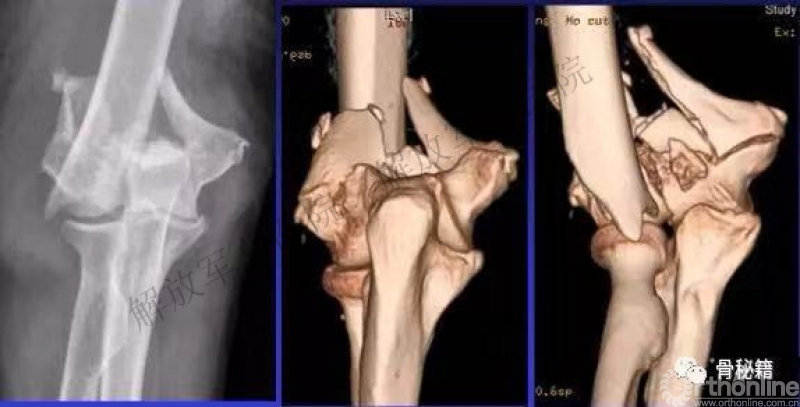

一、详细的术前评估

X线、CT、神经检查、等等。